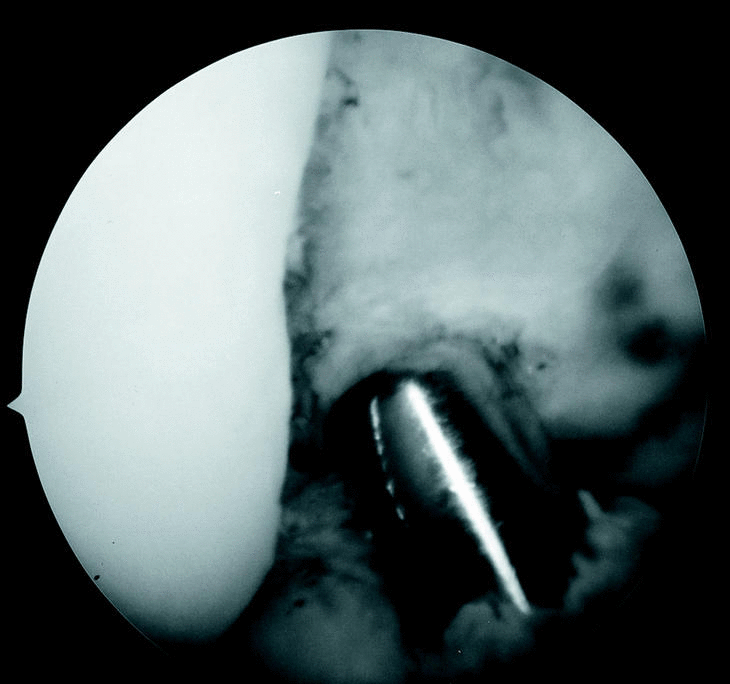

Las reconstrucciones se realizaron mediante técnica monotúnel endoscópica, sin incisión lateral, previa toma del injerto a través de un abordaje cutáneo longitudinal medio centrado en el tendón rotuliano. La EI se limpió de partes blandas con la ayuda de instrumental motorizado. La situación del túnel tibial ha sido descrita previamente11, se utilizó una guía de LCA disponible comercialmente (Acufex®) colocándose el brazo extraarticular en la metáfisis proximal de la tibia, medial a su tuberosidad anterior, mientras que el localizador articular se situaba en la parte más posterior del área de inserción anatómica tibial del LCA, de forma que al taladrar el túnel dejara un ribete de aproximadamente 1 mm de hueso hasta el LCP. Se utilizó un dilatador (Perfixation System for ACL Reconstruction, Instrument Mackar Inc.), de tamaño igual al del injerto previsto, para determinar las dimensiones de la EI (fig. 1) en todo el arco de movilidad de la rodilla y solo se practicó ICP en caso de conflicto de espacio. El túnel femoral se taladró en la zona considerada isométrica, es decir, en la parte más posterior del área de inserción anatómica del LCA, conservando 1 ó 2 mm de hueso cortical posterior3,6,12. Cuando existían dificultades para la correcta visualización de este área se introdujo el artroscopio por el portal infrapatelar, a través de la grasa de Hoffa, maniobra que permite ver bien la EI en toda su profundidad. Una vez introducido el injerto en la rodilla se comprobó su comportamiento durante la excursión articular, fijando a continuación la pastilla ósea proximal en el túnel femoral con un tornillo de interferencia tipo Kurosaka (fig. 2), y tensando el injerto con la rodilla en extensión completa se fijó la extremidad tibial del mismo modo. Para finalizar se rellenó el defecto óseo creado en la rótula con autoinjerto esponjoso y se suturó el paratenon del tendón rotuliano.

Figura 1. Visión artroscópica de la EI. El dilatador de igual tamaño al del injerto preparado calibra el tamaño de la escotadura y preve la posibilidad de conflicto de espacio.